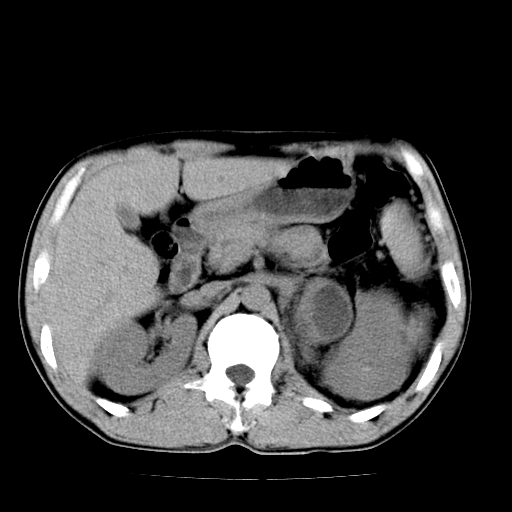

以下是引用天南地北在2007-4-30 13:36:00的发言:[br]支持慢性胰腺炎伴有假性囊肿

以下是引用andymaomao在2007-4-30 14:28:00的发言:[br]支持:1.慢性胰腺炎并假性囊肿形成可能;[br] 2.左肾形态稍增大,旋转不良。